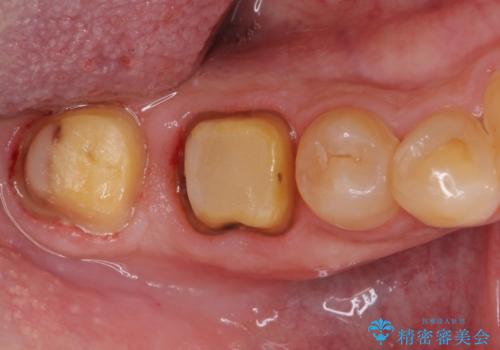

親知らずは速やかに抜歯し、手前の歯とその前の歯に歯槽骨にまで及んだ虫歯が認められたため、歯槽骨を削るなどの歯周外科処置を行うこととしました。

外科処置後の経過を待って、フルジルコニアクラウンにて補綴することとしました。